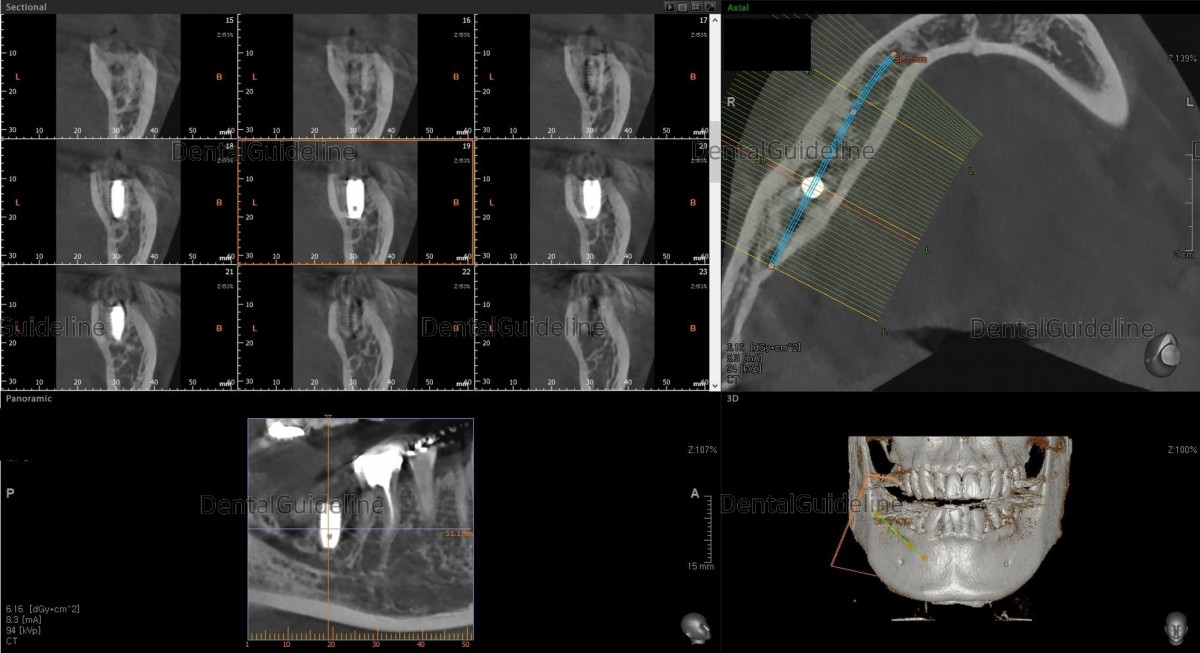

CBCT

Implant placement day after 3 months of extraction.

Initial stability was good enough.

Arum NB1 Ø5*L8.5

post-op CBCT